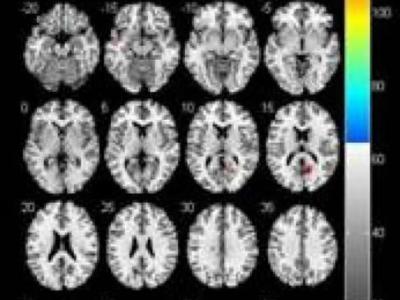

哪些脑区异常可导致帕金森病患者的痴呆?

帕金森病伴痴呆患者较不伴痴呆患者大脑灰质体积显著减少的区域 帕金森是一个多系...